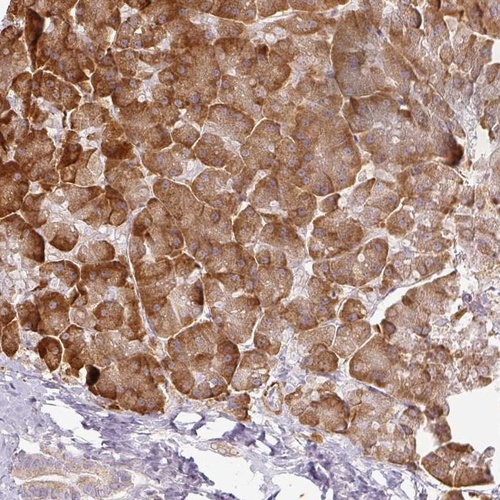

Immunohistochemical staining of human pancreas shows strong cytoplasmic positivity in exocrine glandular cells.